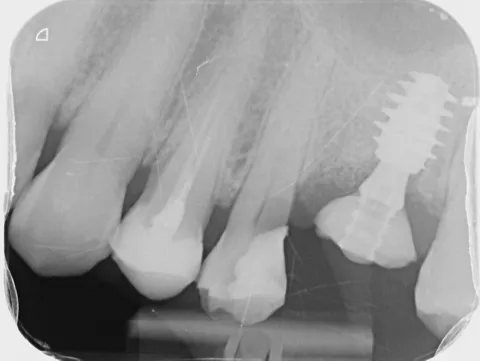

The patient was diagnosed by 3D CT scan and radiograph during a routine control of a classic first molar.  The clinical signs necessitated tooth extraction followed by immediate implantation, socket gap filling and placement of a sealing socket abutment to support anatomical structures.

1. Radiograph of initial situation.

1

4. Radiograph exhibiting a suitable septum for immediate implant placement.

4